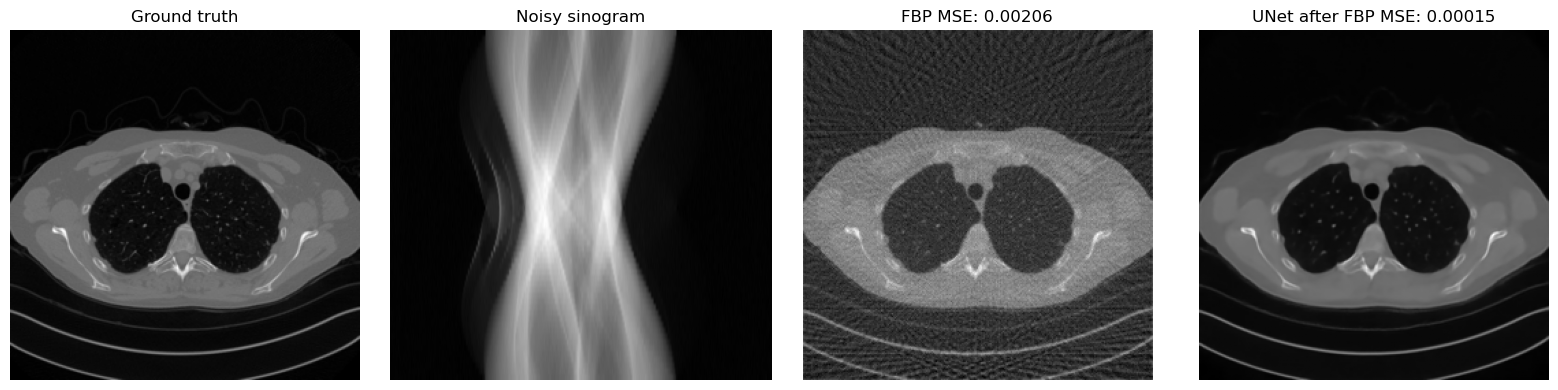

A useful sanity check is to compare the FBP reconstruction and the network output on the same test image. If training has worked correctly, the UNet output should remove part of the streaking artifacts and recover a cleaner image than plain FBP.

mse_fbp = torch.mean((x_fbp - x_true) ** 2).item()

mse_unet = torch.mean((x_rec - x_true) ** 2).item()

plt.title('Ground truth')

plt.title('Noisy sinogram')

plt.title(f'FBP MSE: {mse_fbp:.5f}')

plt.title(f'UNet after FBP MSE: {mse_unet:.5f}')